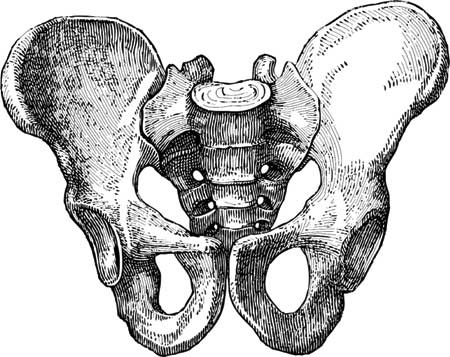

Основой женской половой системы является яичник – небольшой парный орган овальной формы, расположенный в полости таза. Полость эта представляет собой анатомическое пространство, ограниченное костями таза – части скелета, расположенной в основании позвоночника.

Иллюстрация к книге — Твоя жизнь до рождения: тайны эволюции человека [i_008.jpg]

Таз женщины, вид спереди